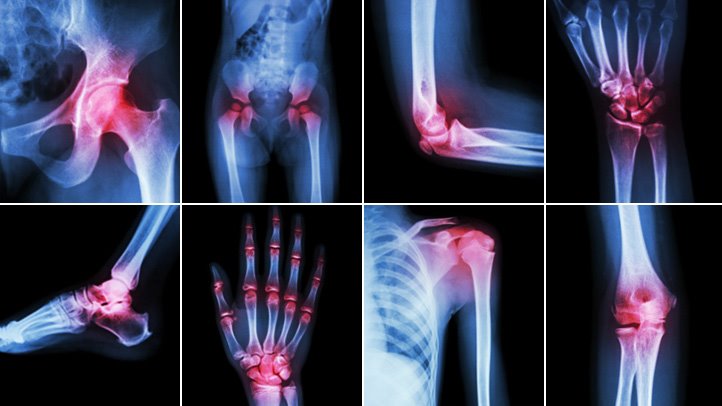

Arthritis affects millions of people all over the world. In fact, from the year 2010 – 2012, approximately 52.5 million adults (22.7%) in the United States were diagnosed with some form of arthritis. Unfortunately, this number is projected to reach 78 million (26%) by the year 2040. Aside from this, arthritis is also considered as one of the leading causes of disability attributed to work limitation and increased risk of falls and injuries (Centers for Disease Control and Prevention, 2016).

Though arthritis usually strikes during the peak of an individual’s most productive years of adulthood, there are several available approaches that can improve the quality of life despite being diagnosed with this disabling condition. This usually begins with our own initiative to increase awareness about the basics of arthritis, including its causes, symptoms and management. To help patients who are either at risk or currently suffering from this condition, this article focuses on the ABCDs of arthritis. Through this, they will be equipped with knowledge on how they can effectively deal with arthritis.